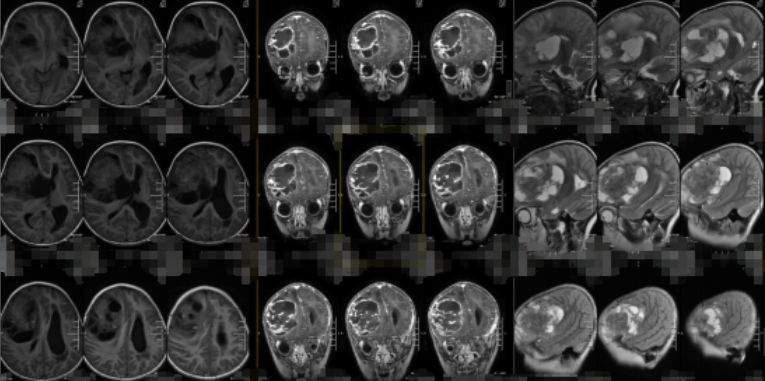

▲术前MR影像检查

我院影像检查提示患儿右侧额叶的占位足有馒头大小,基本占了她脑袋的四分之一。我院大外科首席专家欧阳辉教授和神经外九科主任穆林森详细分析了患儿的病情,一致认为,如果任由肿瘤继续发展下去,患儿随时会有生命危险,建议尽快进行手术。

最终,在欧阳辉教授与穆林森主任的共同努力下,一颗大小为9cm×9cm×8cm的肿瘤被完整切除了。